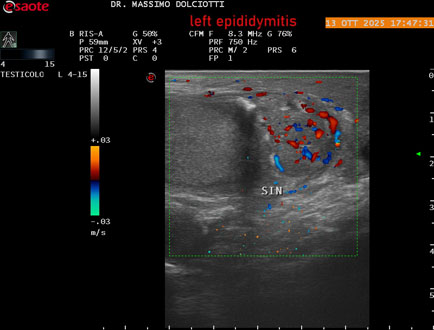

Data inserimento: 14/10/2025

Ecografia del: 13/10/2025

Strumento: Esaote MyLab Eight

Sonda: Lineare Multifrequenza 4-15 MHz

Età Paziente: M 70 anni

Motivazione dell'esame: da 2 giorni dolore al testicolo sinistro.

Commento all'esame: le immagini ed il video documentano l'epididimo sinistro spiccatamente aumentato di volume e di vascolarizzazione, come da flogosi. Didimo sinistro lievemente aumentato di volume. Quadro clinico ed ecografico da ricondurre ad epididimite acuta sinistra.

Conclusioni: epididimite acuta sinistra (acute left epididymitis).

Presentazione: Dr. Massimo Dolciotti - Ancona